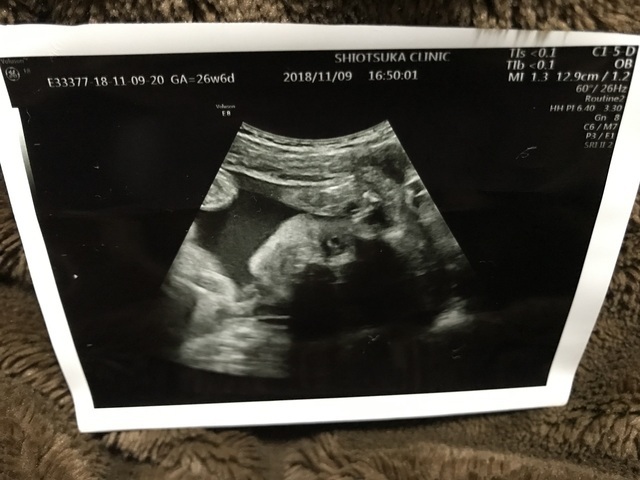

25週0日(25w0d・男の子)|ち75 さん(32歳)

エコー写真撮影時のエピソード:

昔にバンドのボーカルをやっていたり、歌うことも音楽を聴くことも好きなので、妊娠中は今まで行こうと思って行けなかったバンドのライブに行く事にしました。

ライブ中も胎動が激しい曲や何も動かない曲など、好みがあるみたいで面白かったです。エコー写真は歌っている様に、口をパクパクしていた時の息子です。